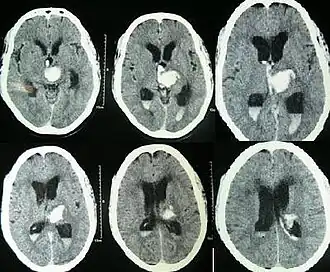

| CT scan showing spontaneous intracerebral hemorrhage with bleeding in the third and both lateral ventricles and hydrocephalus[1] | |

Prognosis is very poor when IVH results from intracerebral hemorrhage related to high blood pressure and is even worse when hydrocephalus follows.[1] It can result in dangerous increases in ICP and can cause potentially fatal brain herniation.[1] Even independently, IVH can cause morbidity and mortality. First, intraventricular blood can lead to a clot in the CSF conduits blocking its flow and leading to obstructive hydrocephalus which may quickly result in increased intracranial pressure and death.[15] Second, the breakdown products from the blood clot may generate an inflammatory response that damages the arachnoid granulations, inhibiting the regular reabsorption of CSF and resulting in permanent communicating hydrocephalus.[2][15]